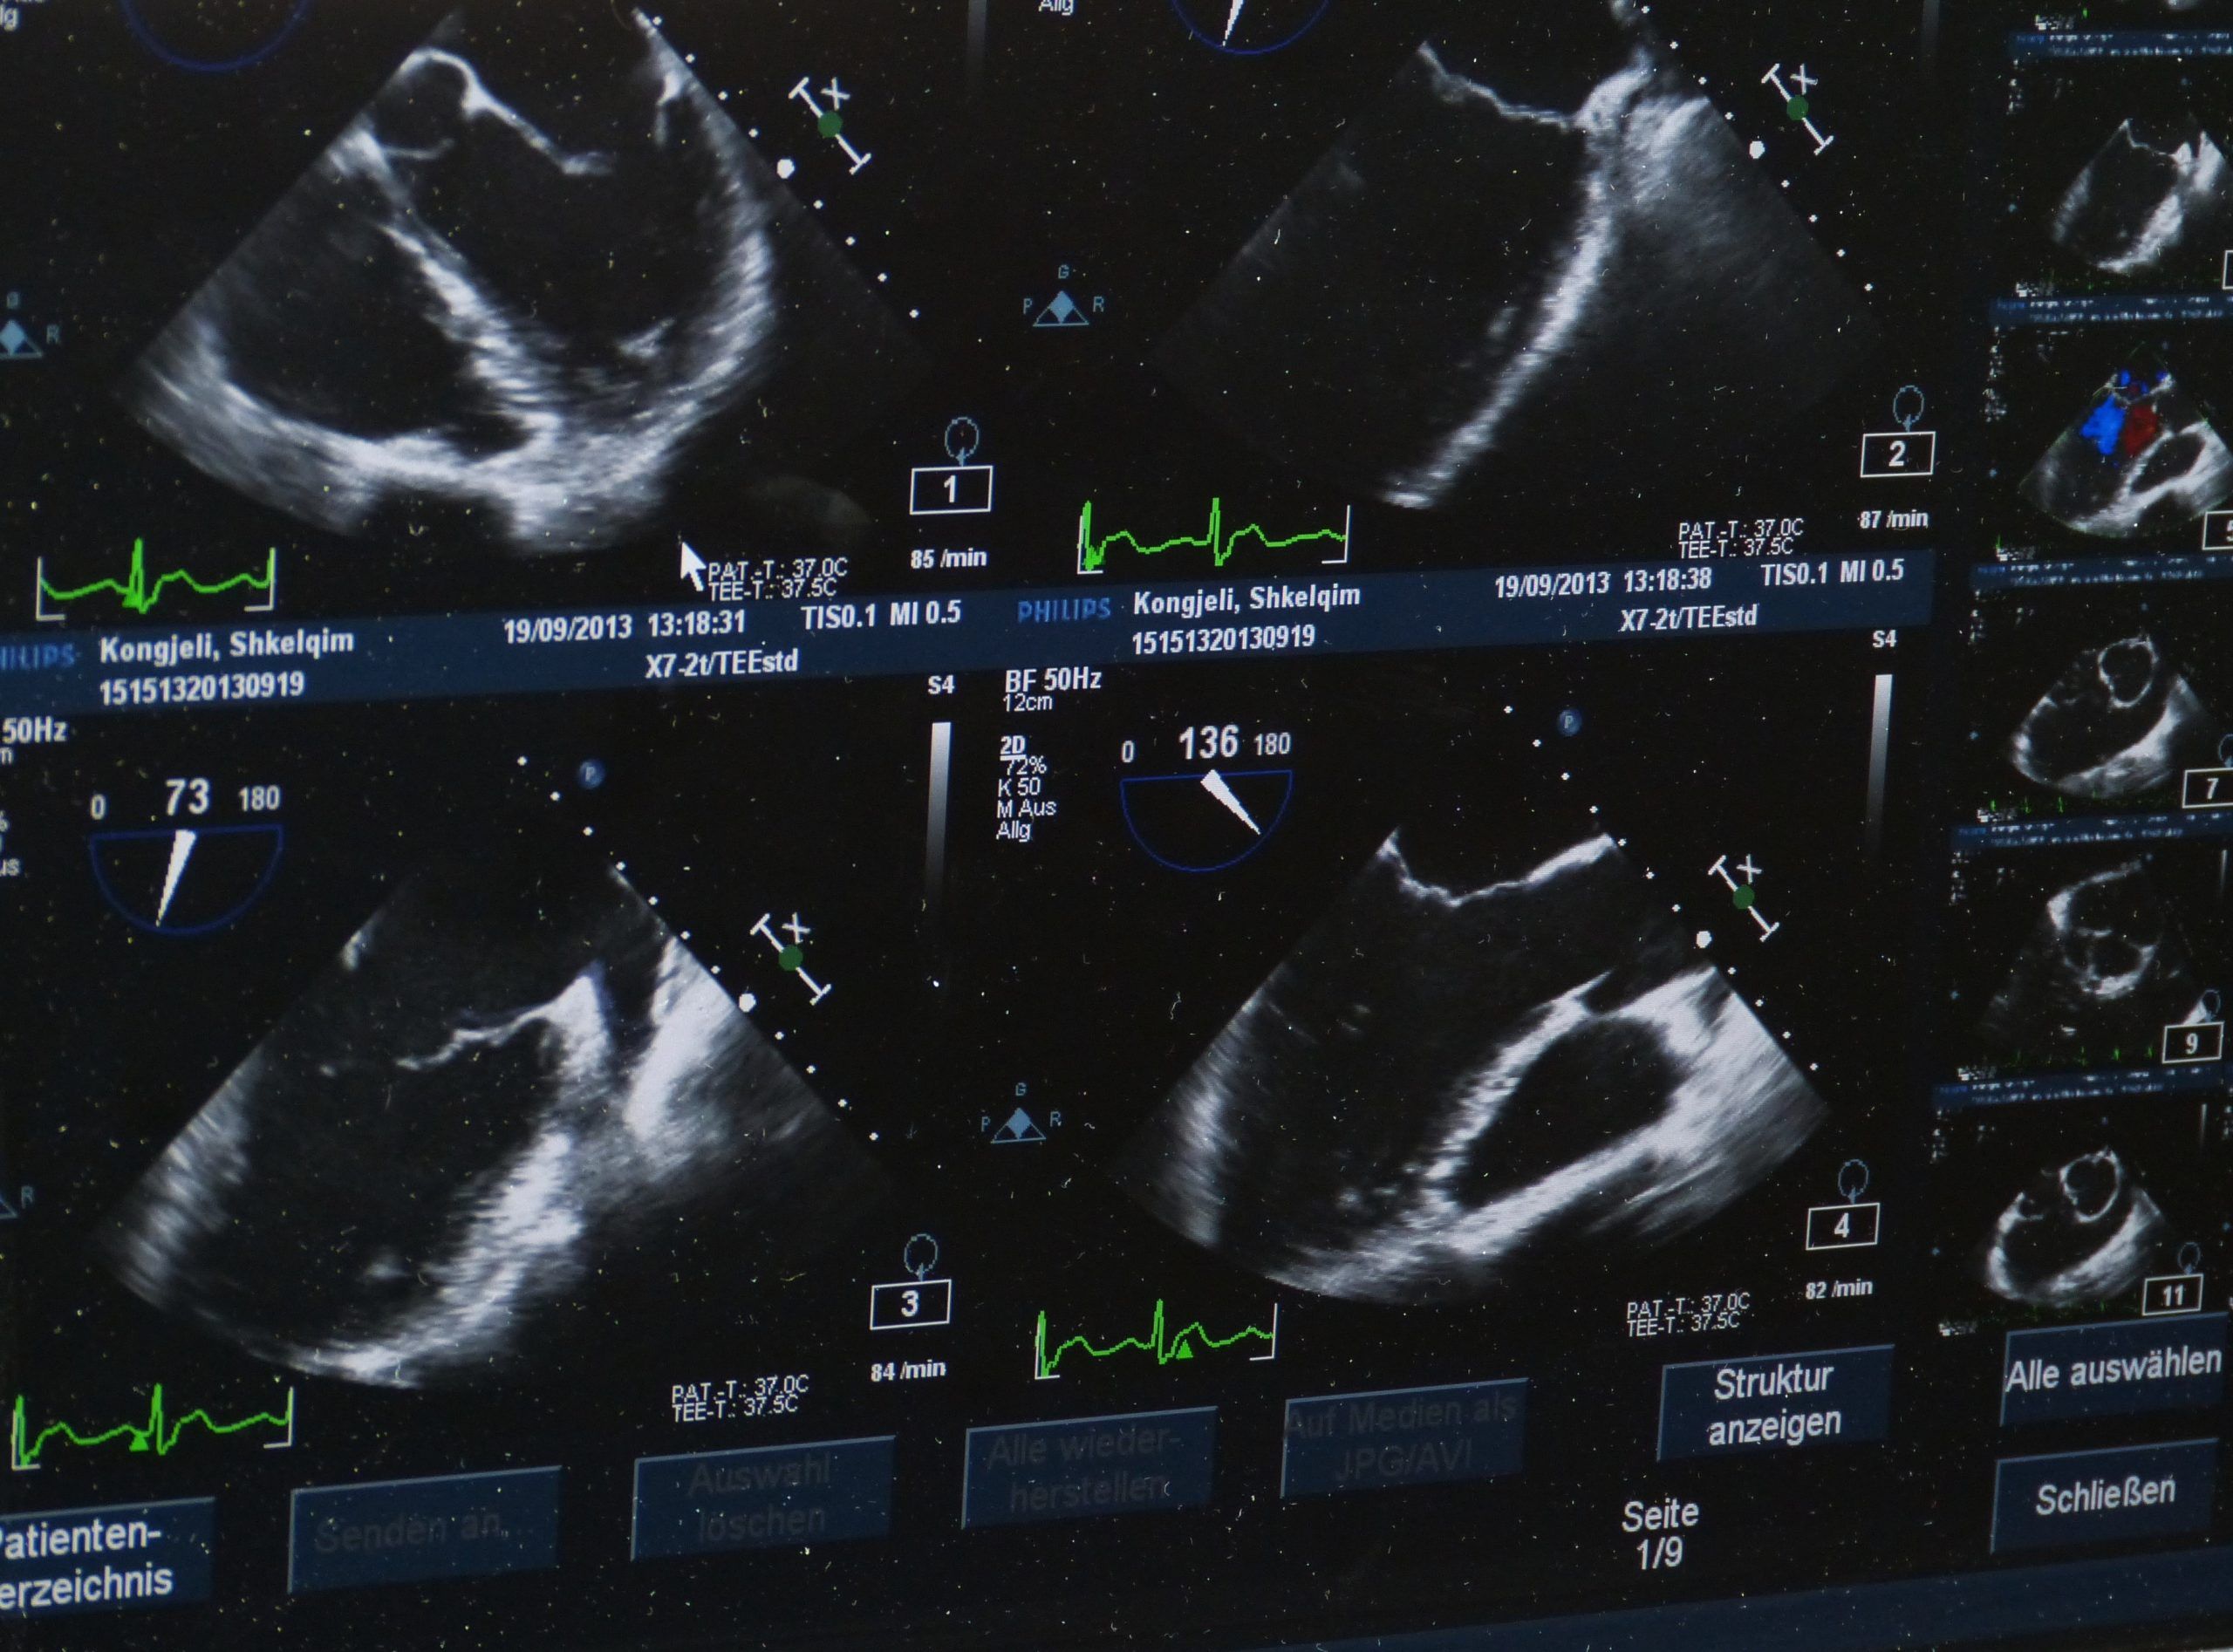

Наш путь начался с осознания масштаба проблемы. Представьте себе врача, которому ежедневно приходится просматривать десятки научных статей, клинических отчетов и историй болезни. В этом море информации легко упустить важные детали, особенно когда речь идет о новых методах лечения или потенциальных побочных эффектах. Именно здесь на помощь приходят системы анализа текста, способные автоматически извлекать ключевую информацию и предоставлять ее в удобном для восприятия формате.

Чтобы проиллюстрировать возможности нашей системы, приведем несколько практических примеров:

- Анализ научных статей: Система может автоматически извлекать из научных статей информацию о новых методах лечения и их эффективности.

- Анализ клинических протоколов: Система может проверять, соответствуют ли действия врача действующим клиническим протоколам.

- Анализ историй болезни: Система может выявлять риски и предлагать дополнительные обследования или консультации.

Эти примеры показывают, что системы анализа медицинских текстов могут быть полезны как для врачей, так и для пациентов.